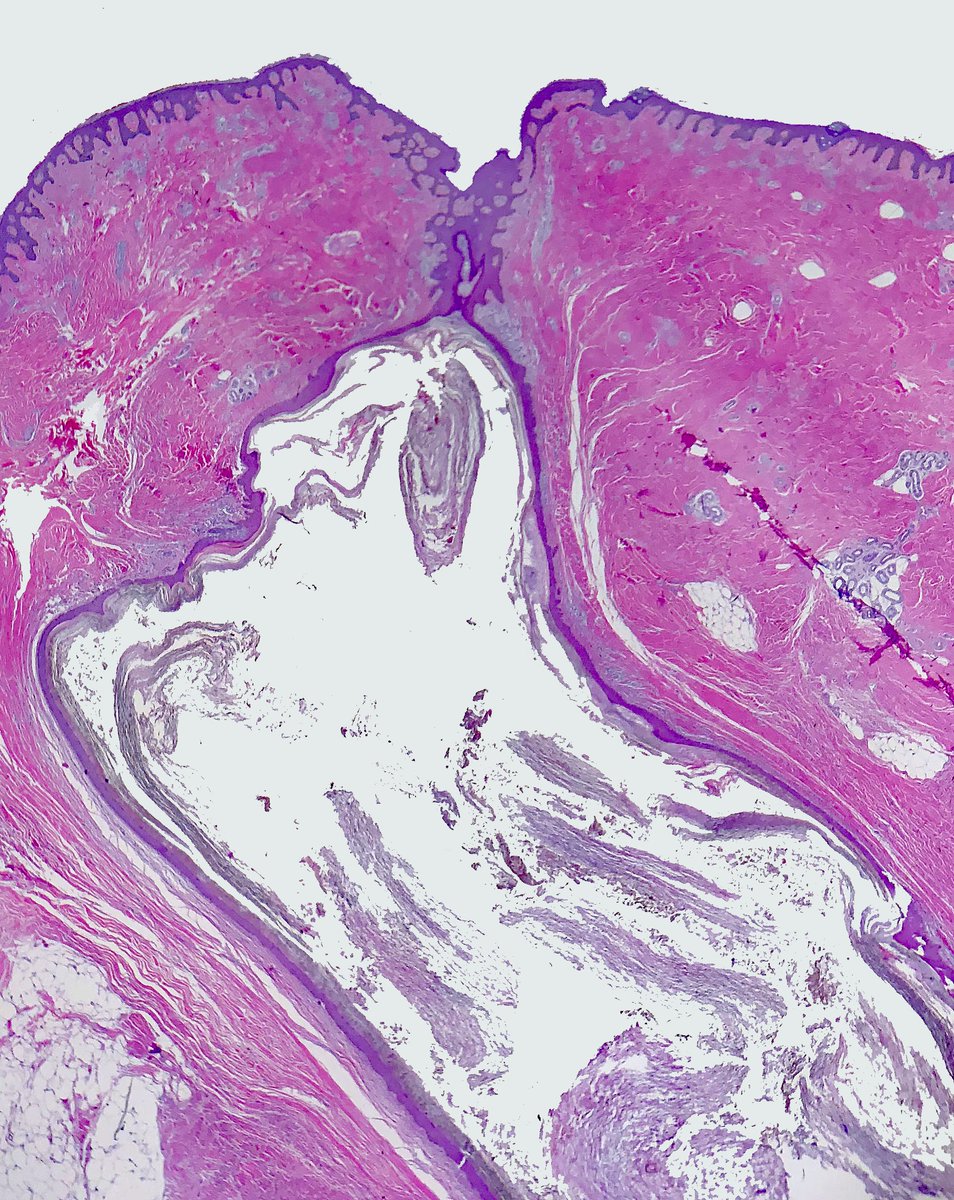

This EIC really puts the "inclusion" in epidermal inclusion cyst. These are often submitted as "sebaceous cysts."

#pathology#dermpath#Dermatology pic.twitter.com/Ld0zBJIumf